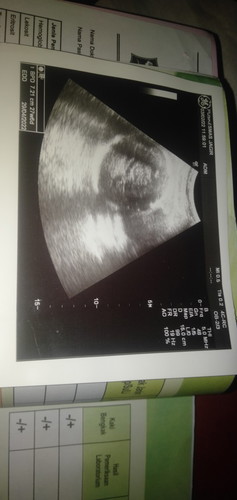

Usg 2D tolong yang tau bisa bantu jelaskan bund

Maaf bund, kalau ada yg tau bisa bantu jelaskan kah? Kmrn cek usg di puskesmas. Dokternya hpan mulu, cm dijelasin posisi kepala udah mapan pdhl blm genap 7bln. Kl saya ga tanya ga bakal dijelasin, tp kmrn ada aja yg kelupaan mau ditanya aplg liat dokternya cuek. Ini dikasih foto cm 1 yg posisi ini. Jd sy nya agak kurang puas gt dan ga ngerti😭 Kmrn di info bb janin 1,06 gr tp ditulis dibuku kia 1,63 gr 😢 Sy jg gatau ini ada lilitan apa engga, bener² ngeblang pas usg. Cm keinget tanya jumlah air ketuban sm letak plasenta. Maaf ya bund kl ada yg ksel sm pertanyaan saya. Barangkali ada yg tau bisa bantu jawab. Trims bund #seriusnanya #bantusharing #ingintahu #pleasehelp #firstbaby